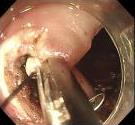

• 可旋转重复开闭软组织夹联合外科尼龙缝合线法闭合结直肠内镜黏膜下剥离术后缺损的临床应用价值

2025, 31(12):77-82. DOI: 10.12235/E20250091

摘要 (77) HTML (65) PDF 1.86 M (64) 评论 (0) 收藏

摘要:目的 探讨可旋转重复开闭软组织夹联合外科尼龙缝合线法(ROLM)闭合结直肠内镜黏膜下剥离术(ESD)后黏膜缺损的临床疗效。方法 回顾性分析2024年1月-2024年6月15例在南京医科大学附属常州市第二人民医院因早期结直肠肿瘤行ESD,并采用ROLM闭合黏膜缺损患者的临床资料。观察患者病灶相关情况(病灶部位、缺损最大径和术后病理)、手术相关情况(术后缺损成功闭合率、钛夹使用数量、ROLM缝合时间和住院时间)、术后并发症发生情况和术后随访情况。结果 术后缺损成功闭合率为100%。病灶长径3.0~6.0 cm,平均(3.7±0.8)cm。缺损部位:回盲部1例,升结肠6例,横结肠肝曲1例,降结肠2例,乙状结肠3例,直肠2例。术后病理为:管状腺瘤8例,黏膜下囊肿1例,管状绒毛状腺瘤5例,胃肠道间质瘤1例。钛夹使用数量为7~20枚,中位数为11(10,13)枚。ROLM缝合时间为13~37 min,平均(19.3±6.5)min。住院时间4~9 d,平均(6.5±1.2)d。术后无出血、穿孔、感染和消化道狭窄等并发症发生。术后3~6个月复查肠镜,手术创面均愈合良好。结论 ROLM能够安全、有效地闭合结直肠ESD后黏膜缺损。值得临床推广应用。